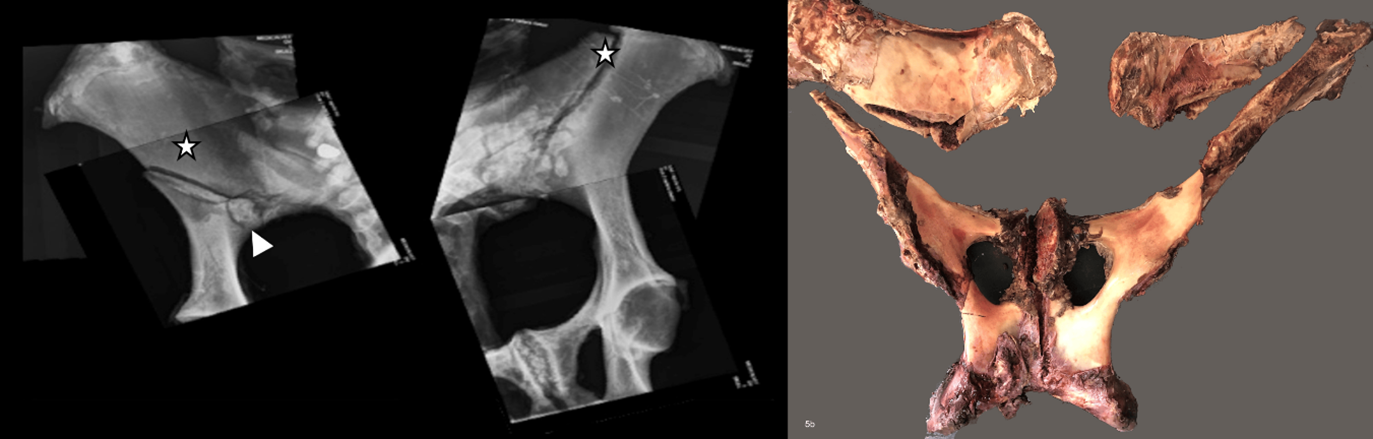

Examen post mortem y radiográfico

Tras la eutanasia se efectuó la necropsia completa. Se realizaron radiografías digitales de la pelvis (Sound Eklin digital system, Next II) luego de remover los músculos, debido al marcado edema y aumento de volumen muscular que dificultaban la visualización. Esta técnica permitió reconstruir y seguir las líneas de fractura sobre la pelvis (figuras 5).

Después de la radiografía se disecó con cuidado la pelvis para examinar las superficies óseas. Se desarticularon y examinaron macroscópicamente las articulaciones sacroilíacas, los acetábulos y la sínfisis pélvica; también se examinaron el sacro, el hueso coxal y la columna vertebral lumbar. El ilion, incluidos el tubérculo sacro y el tubérculo coxal, se seccionó de forma transversal con una sierra de cinta en láminas de aproximadamente 1 a 2 cm de espesor, mientras que la sínfisis pélvica, el pubis y el isquion se cortaron en el plano sagital.

Todos los conjuntos de secciones seriadas fueron examinados, fotografiados con cuidado y se registró la ubicación anatómica, el tipo y el tamaño de las lesiones.

Macroscópicamente se observó una fractura ilíaca completa, desplazada y oblicua de forma bilateral; ambas se originaban en el borde caudal de la diáfisis ilíaca proximal, a nivel de la articulación sacroilíaca. La fractura izquierda atravesaba en dirección lateral y la derecha en dirección cráneo-lateral, alcanzando la tuberosidad coxal. La fractura izquierda tenía origen en un pequeño fragmento óseo y presentaba un defecto único, lineal, con bordes bien definidos. La línea de fractura derecha era más larga, irregular y de bordes redondeados (figuras 6), acompañada de una proliferación perióstica extensa, indicativa de fractura por fatiga o estrés.